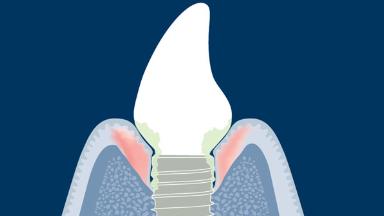

O tratamento com implantes é altamente bem-sucedido, conforme documentado na literatura científica. No entanto, os clínicos devem esperar ver complicações em sua prática diária. As complicações associadas à mucosa ou osso peri-implantar circundante são chamadas de complicações biológicas. Elas ocorrem quando há um desequilíbrio entre o desafio do biofilme bacteriano nos tecidos ao redor do implante e a defesa do hospedeiro, resultando em um processo inflamatório. As complicações biológicas abordadas neste módulo são as doenças peri-implantares, denominadas mucosite peri-implantar e peri-implantite, que podem ocorrer em torno de implantes osseointegrados. Portanto, é importante que o clínico seja capaz de diagnosticar mucosite e peri-implantite peri-implantares e entender as etapas para o manejo dessas complicações.